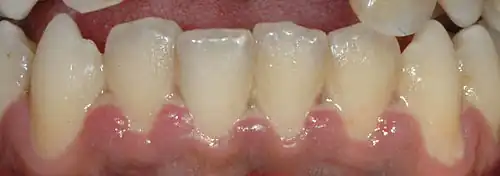

La gingivite ulcéronécrotique (GUN) se caractérise par des lésions nécrotiques au niveau de la gencive marginale, des zones de nécrose recouvertes d'une pseudomembrane blanc jaunâtre de consistance molle faite de leucocytes et de bactéries (la zone ulcéreuse est sous-jacente). L'ulcère nécrotique commence au sommet de la papille et la sépare en un versant vestibulaire et un lingual. Il y a une gingivorragie spontanée, une halitose fréquente et parfois des adénopathies.

Au début, une seule papille est touchée mais l'atteinte peut s'étendre aux autres papilles avec un lien nécrotique. La nécrose peut s'étendre sur toutes les faces vestibulaires, plus rarement sur les faces linguales ou palatines.